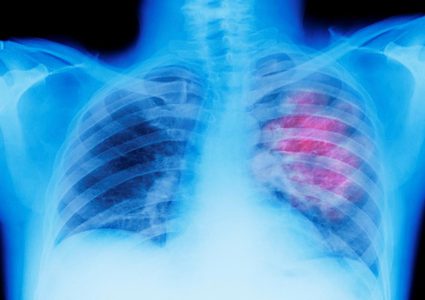

أعلن نائب المدير العام لمؤسسة الدراسات المتقدمة، ألكسندر بانفيلوف، أن العلماء الروس ابتكروا جهازا يمكن بواسطته تشخيص الإصابة بالسل وسرطان الرئة مبكرا. وقال رئيس قسم …

أظهرت نتائج أولية أن فحص دم تجريبيا تطوره شركة جريل يبشر باكتشاف سرطان الرئة في مراحله المبكرة استناداً إلى الحمض النووي العائم الذي يطلقه الورم في الدم. …